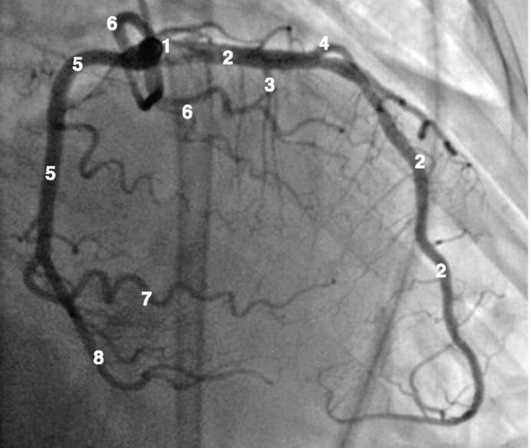

Рентгенанатомия коронарных артерий при правом, левом и сбалансированном типах кровоснабжения миокарда представлена на коронарограммах (рис. 1-1-1-30, см. с. 16-30). Исследование проводят под мониторным контролем ЭКГ и артериального давления. При возникновении сложных нарушений ритма, снижении артериального давления более чем на 25% от исходного, ишемических изменениях на ЭКГ исследование прерывают и проводят соответствующую терапию. Адекватное обезболивание и кислородотерапия, инфузии нитроглицерина и β-блокаторов, атропина и симпатотмиметиков - это не полный перечень медикаментозной терапии, которая может сопровождать выполнение вмешательств.

Коронарограммы при различных типах кровоснабжения миокарда

Левая коронарная артерия

Правая коронарная артерия